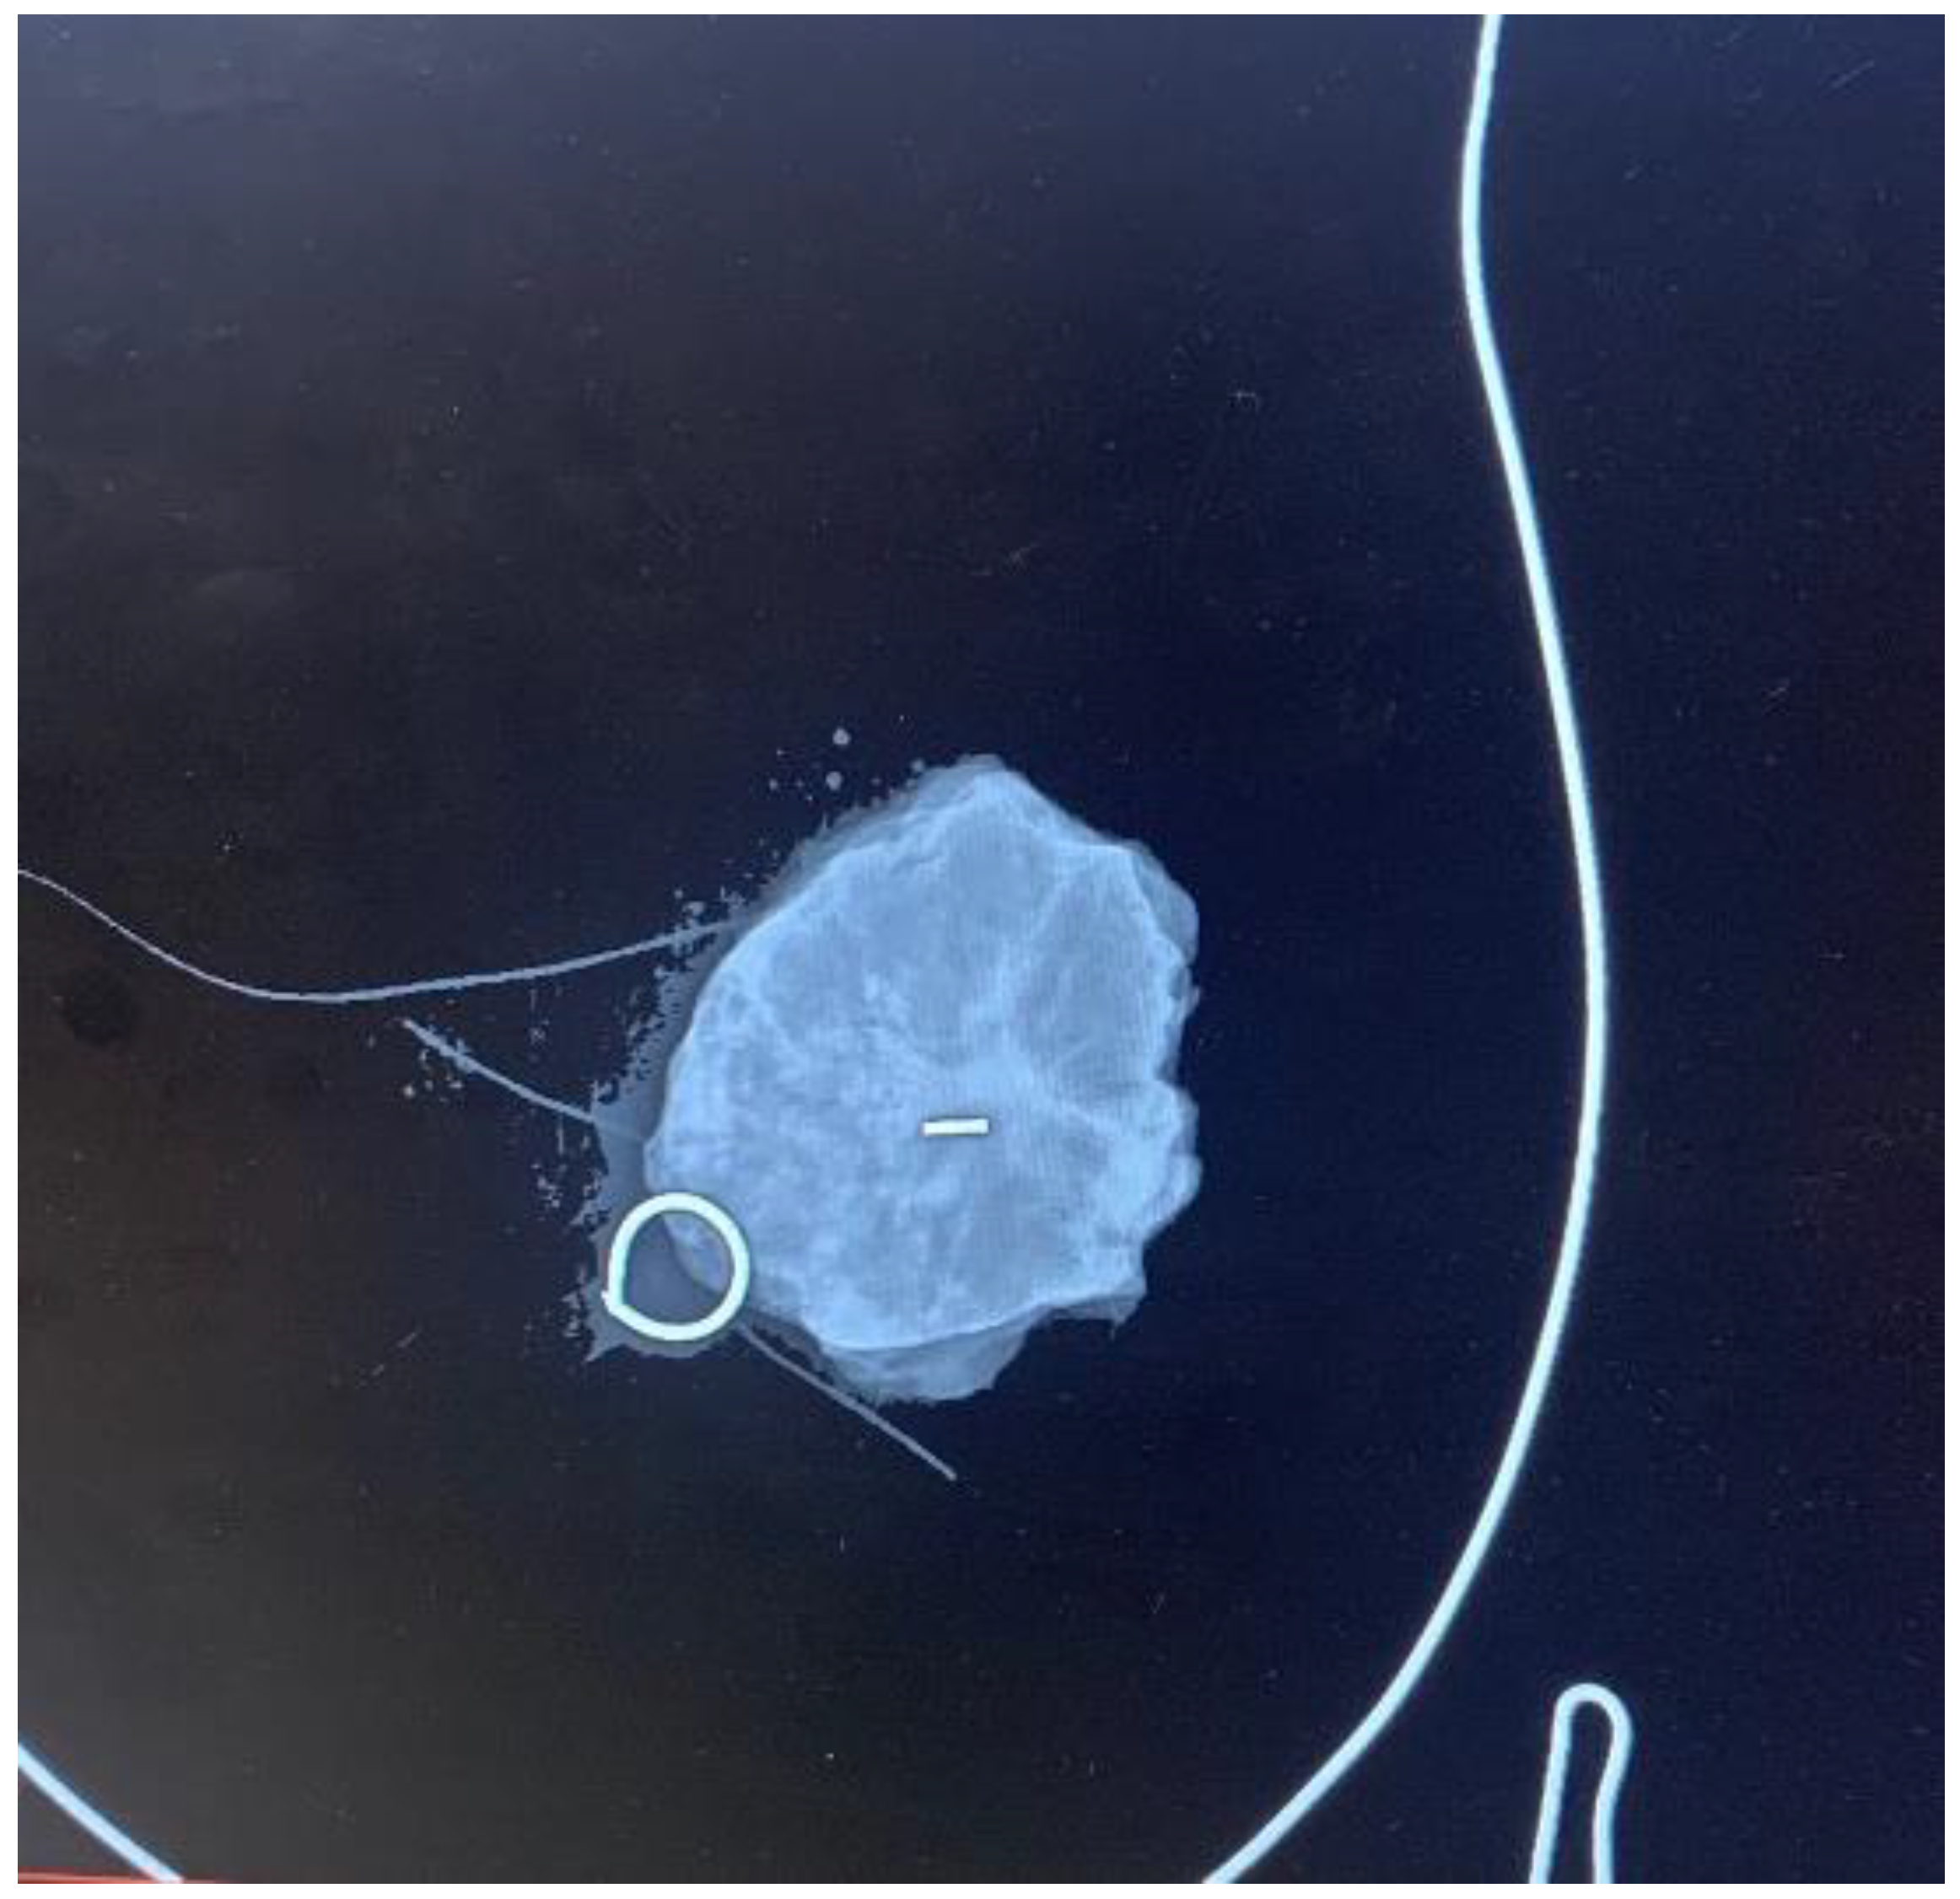

Each patient underwent a mammogram and an ultrasound at diagnosis. Magnetic resonance was performed based on the radiologist’s criteria if necessary to complete the study. Upfront treatment was decided upon the multidisciplinary committee according to international guidelines [11]. Both wires and MSs were placed by four experienced breast radiologists under ultrasound guidance, as stereo placement was not available at the time of the study. MSs were placed using local anesthesia. A control mammogram was performed after placing the wire or the MSs in all cases and could be visualized during the procedure in the operating room (Figure 1). Wires were placed on the same day of the surgery; each patient first went to the radiological room, had the wired placed, and then was taken to the surgery room or to their hospital room until the theater was available. MSs were placed independently of the surgery day, always less than 30 days before surgery, as MSs were initially approved for placement up to 30 days prior surgery (although currently, MSs have no time limit between placement and surgery). Every surgery was performed by one of the six experienced breast surgeons of the breast unit, and an informed consent form was signed before surgery [3]. MSs were intraoperatively localized using the Sentimag® probe. Every surgical specimen, including wire- and MS-guided specimens, was evaluated with a mammogram to confirm adequate excision of the lesions (Figure 2). If the mammogram of the surgical specimen showed close margins, the surgeon was informed, and the margin was extended in the same surgery.

Figure 2.

Control mammogram of the surgical specimen. The surgical specimen is positioned on a methacrylate plate featuring a breast drawing to orient it anatomically.